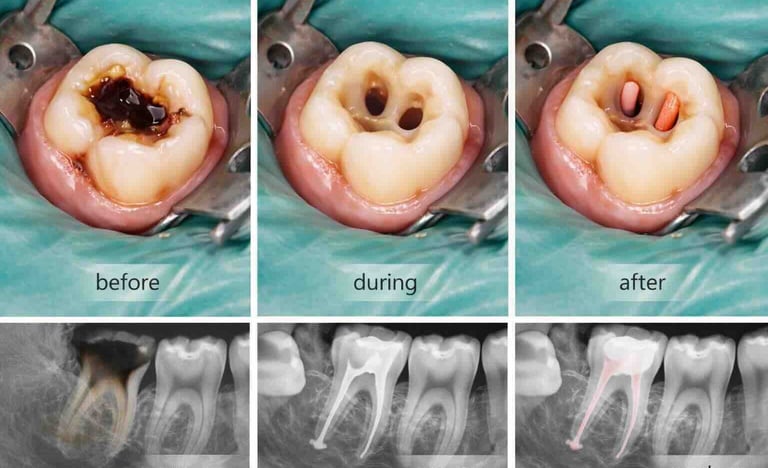

Root canal treatment removes infected or damaged pulp from inside a tooth. The pulp contains nerves and blood vessels, and infection can cause pain, swelling, or abscesses. During the procedure, the dentist cleans out the infection, shapes the root canals, and fills them with a safe material. Finally, the tooth is restored with a crown or filling to protect it. Root canals prevent infection from spreading and help keep your natural tooth

Examination & X-rays – determine the extent of infection or damage

Cleaning the pulp – remove infected tissue from inside the tooth

Shaping & filling – shape canals and fill with biocompatible material

Temporary or permanent restoration – crown or filling placed to protect the tooth